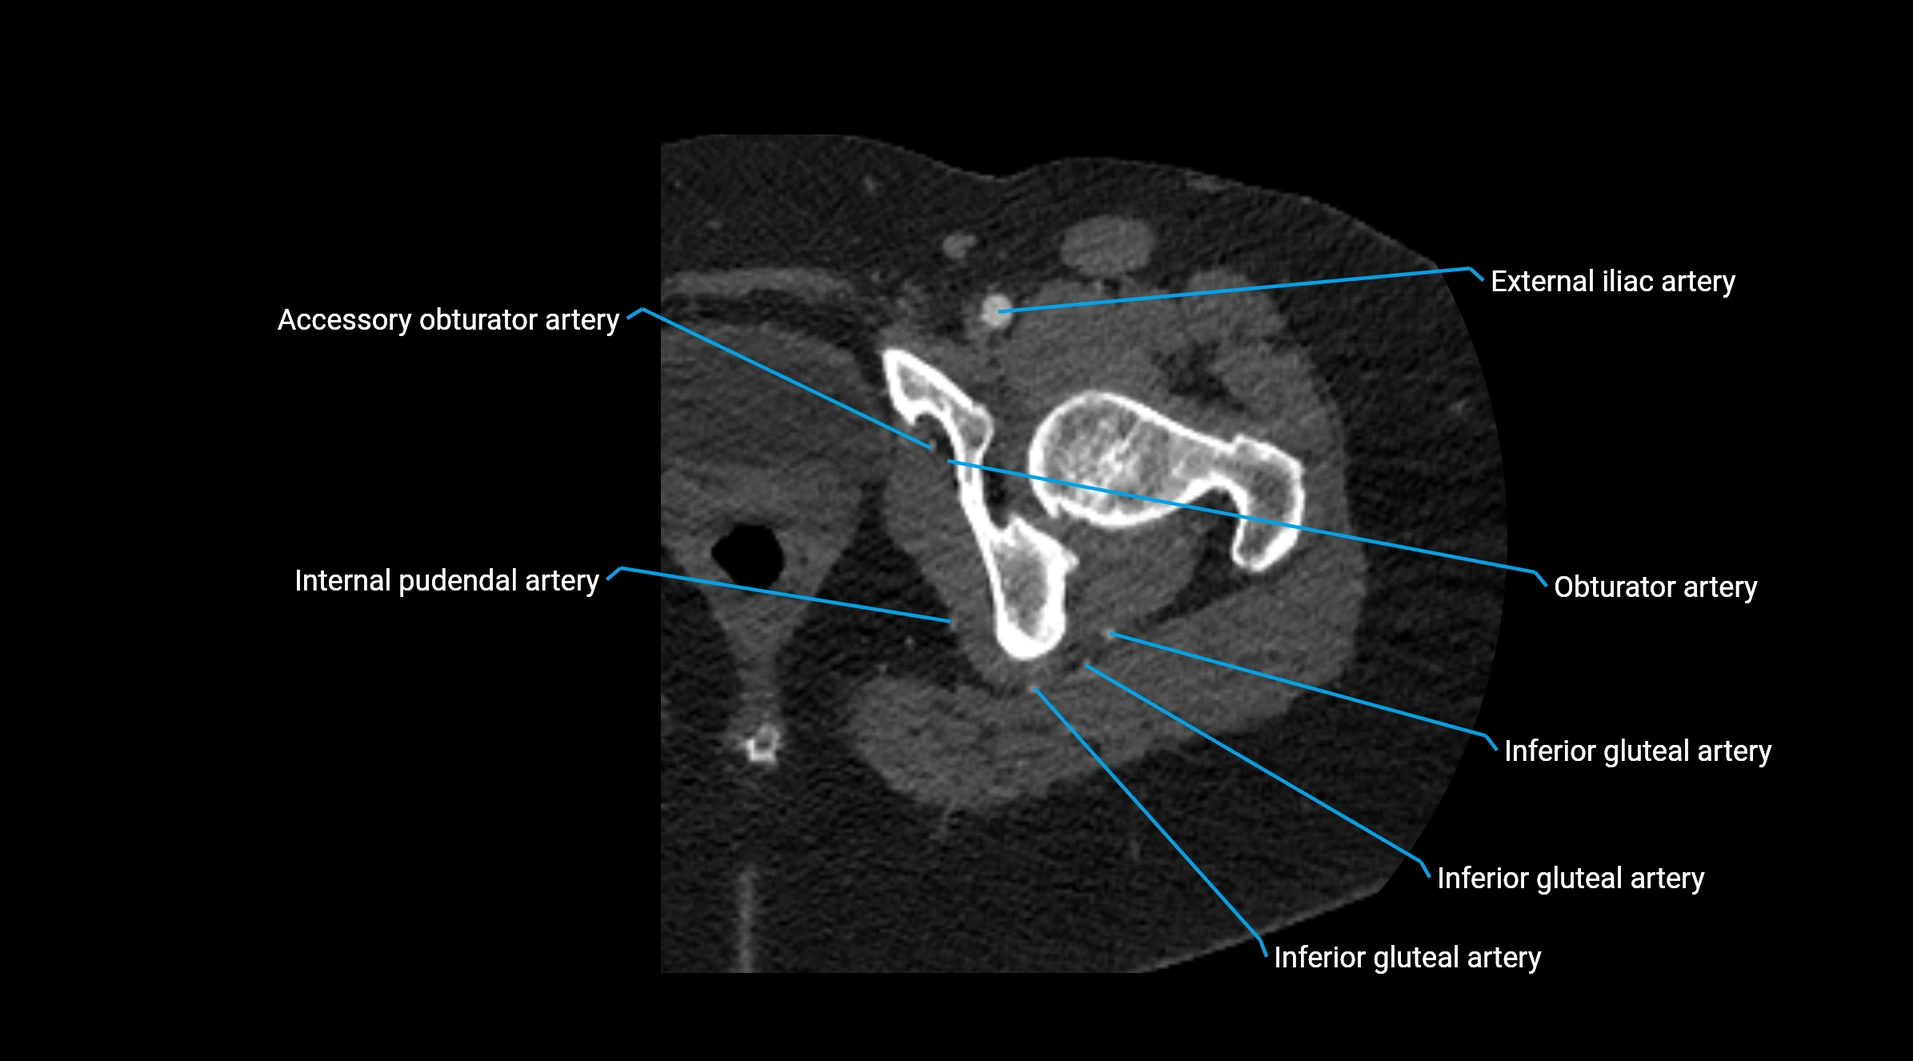

CT images

image

Contrast-enhanced CT (CTA):

• Gold standard for abdominal aortic imaging

• Provides excellent detail of lumen, wall, aneurysm, thrombus, and branch vessels

• Multiplanar and 3D reconstructions help in aneurysm measurement, stent graft planning, and dissection evaluation